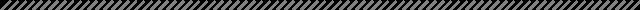

11月10日,受益于“我为群众办实事”实践活动——“晋江市髋膝关节置换救助工程”项目,尤大叔入院进行手术治疗??悸堑交颊呦ス亟谘现夭晃榷?、韧带功能丧失,上海市第六人民医院骨科副主任、主任医师,上海六院福建医院副院长沈灏教授选择了旋转铰链膝对患者行全膝关节置换术。

12日,手术顺利完成,尤大叔患者膝关节的运动功能恢复良好,手术后第一天就开始进行床上屈伸活动,第二天开始逐渐下地站立、行走。据了解,尤大叔将于11月16日出院。

▲术后影像